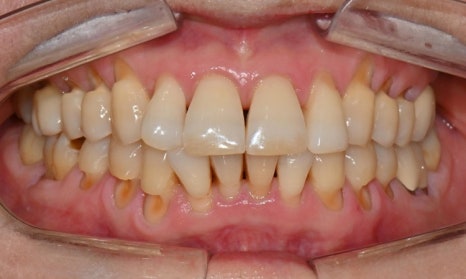

본 환자는 70세 여환으로 가만히 입을 다물고 있을 때 화난 것 처럼 보인다고 해서 튀어나온 앞니를 조금 넣고 싶다는 주소로 내원하셨습니다. 전체적인 치아 및 잇몸 상태를 검진해본 결과, 마모되어 깨진 치아도 있었고, 치경부(치아와 잇몸 사이 경계 부위)가 마모되어 파여 있는 부위도 많았습니다.

2025.2.3. 초진